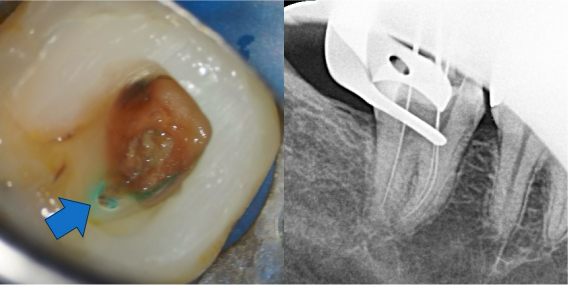

根管治療1回目

ラバーダムを装着し深い虫歯を除去すると、神経まで達していたことが確認できました。そのまま虫歯を完全除去し、歯の根の長さを測定後、ニッケルチタンファイルを使用して歯の内部の機械的拡大を行い、薬を入れて初回の治療は終了しました。

痛みが強い状態の場合、基本的には2回にわけて根管治療を行っていきます。